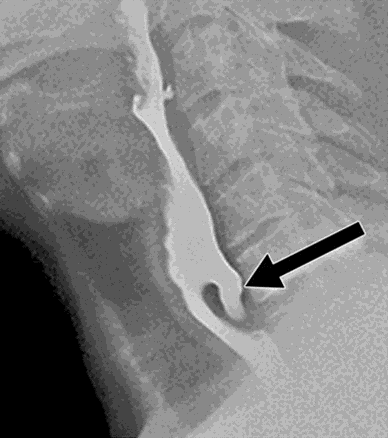

An esophagogastroduodenoscopy (EGD) was performed, and initial examination revealed a dilated esophagus with Zenker’s diverticulum measuring 4.2 cm arising from the proximal esophagus at the pharyngoesophageal junction (Figure 1). Mild proximal esophageal dilation was observed, likely due to outflow obstruction caused by the diverticulum. No strictures or stenosis were identified in the mid or distal esophagus, and the gastroesophageal junction appeared normal. While a video swallow study was not performed, it may have provided additional information into the extent of this patient’s oropharyngeal dysphagia, particularly relevant in light of his symptoms and underlying history of CMT.

Figure 1: Clinical picture from [15] showing large Zenker’s diverticulum causing esophageal obstruction.